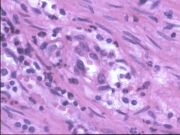

| 2021年12月10日 (五) 13:14 | 12号切片-异物肉芽肿(虫卵及异物巨细胞)-镜下观3.jpg (文件) |  |

109 KB | Cirno.9 | 基于MsUpload的文件上传 | 1 |

| 2021年12月10日 (五) 13:14 | 12号切片-异物肉芽肿(虫卵及异物巨细胞)-镜下观2.jpg (文件) |  |

117 KB | Cirno.9 | 基于MsUpload的文件上传 | 1 |

| 2021年12月10日 (五) 13:14 | 12号切片-异物肉芽肿(虫卵及异物巨细胞)-镜下观1.jpg (文件) |  |

161 KB | Cirno.9 | 基于MsUpload的文件上传 | 1 |